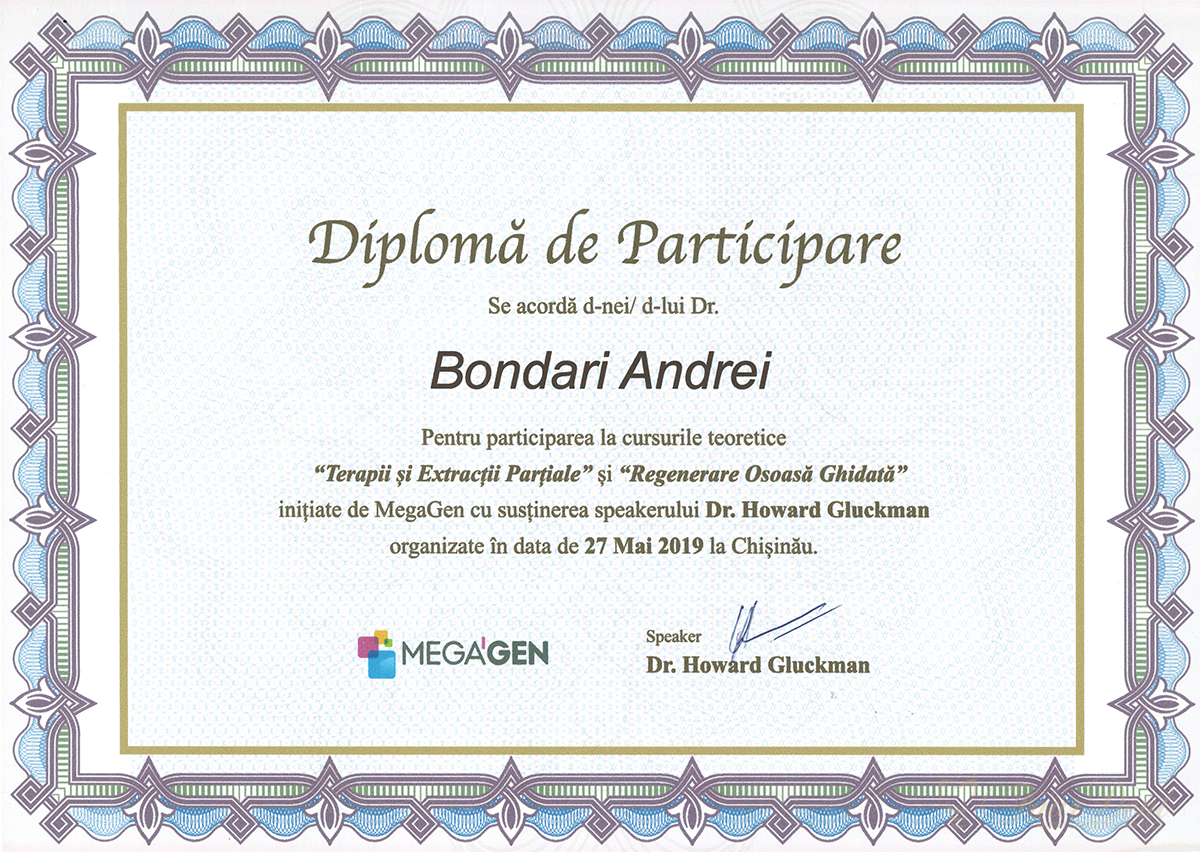

Experiență, profesionalism și tehnologie modernă pentru zâmbetul tău perfect în Chișinău, Buiucani. Descoperă serviciile noastre de dantură fixă sau programează-te pentru o consultație.

Specialiști cu experiență